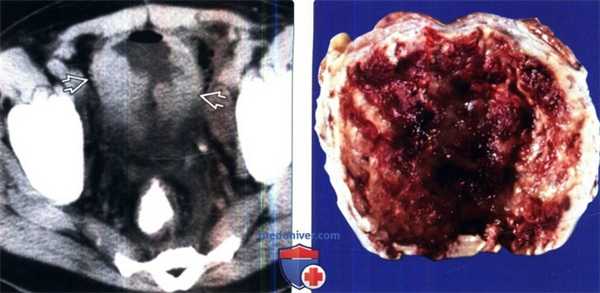

(Слева) КТ мочевого пузыря с контрастированием: неравномерное утолщение стенки мочевого пузыря, похожее на объемное образование. Данные признаки не позволяют отличить образование от уротелиального рака, поэтому требуется биопсия.

(Справа) Фотография среза образца удаленной ткани: рыхлая поверхность с кровоизлиянием и бросающееся в глаза утолщение стенки. Мочевой пузырь является наиболее частым местом возникновения малакоплакии. Следом идут паренхима почки, верхние отделы мочевыводящих путей, предстательная железа и уретра.